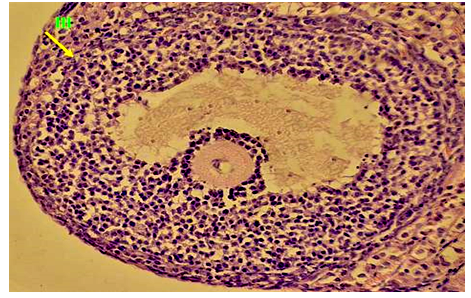

The Oocyte has a large size and spherical shape with central positioning nuclei [19]. fig. 1. Granulosa cells in the Graafian follicles have a high divisive-capacity with exceeding the rest of the developing ovarian follicles (fig. 2).

Fig. 1: Transverse section of Graafian follicles in the control group. (H & E x400) Fig. 2: Transverse section in the early stages of division in the Graafian follicles in the control group (Ki67x400)